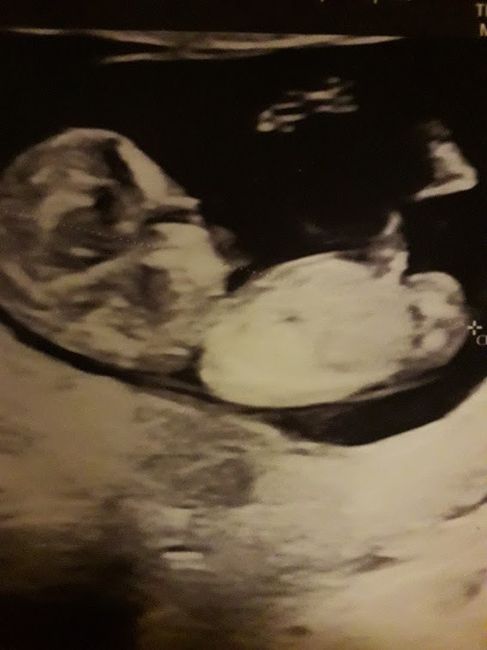

Mancano ancora tantissime settimane alla morfologica, che avrò il 15 Luglio, mi ritrovo spesso a fantasticare se sarà Filippo o Lucrezia, io mi sento maschio ma non si sa mai.

Mi affido a voi esperte di Nub Theory, cosa dite maschio o femmina??